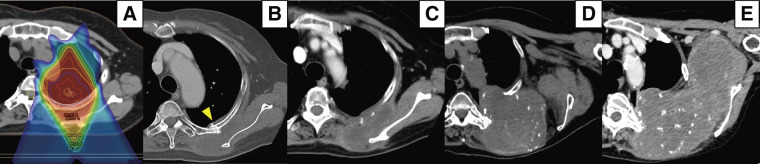

Chronic expanding hematoma (CEH) is defined as a hematoma that gradually expands over months to years. An 82-year-old female underwent proton radiotherapy for left upper lobe lung cancer 10 years previously. Two years after the therapy, a hematoma developed from the left 3rd to 5th dorsal rib fractures and gradually expanded, causing contraction of the left shoulder. Transcatheter arterial embolization was performed; however, the hematoma continued to expand with thrombocytopenia, and the platelet was decreased to 4.2 × 104/μL. Computed tomography showed a 17.2 × 14.0 × 10.0 cm mass between the left scapula and left dorsal ribs. The CEH of the thorax was completely excised with combined resection of the 3rd to 5th ribs, while the brachial plexus was preserved. Postoperatively, the platelet completely recovered and she could raise her left arm. A complete excision with surrounding organs preserved is the strategy used in the treatment of CEH of the thorax.